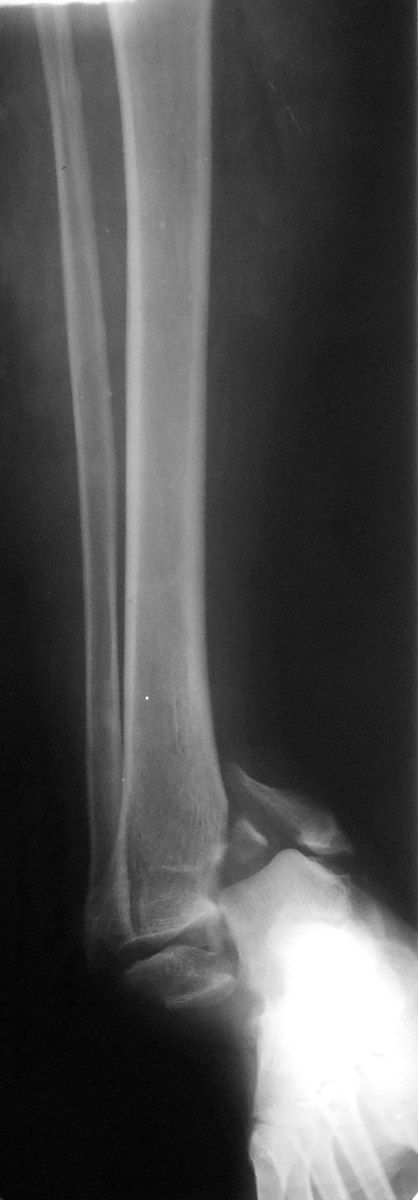

В приложении рентгенограмма первичная. После чего стала ясна сомнительность перелома пилона))) Перелом лодыжек с импрессией суставной поверхности большеберцовой кости в области внутренней лодыжки. На выполненном вчера КТ голеностопного сустава: в просвете сустава определяется клиновидной формы фрагмент костной плотности размером до 13,5х3,5 мм, находящийся в задне-латеральных отделах сустава.

Боковая проекция. Боковой проекции первичных рентгенограмм нет, утеряны больным.